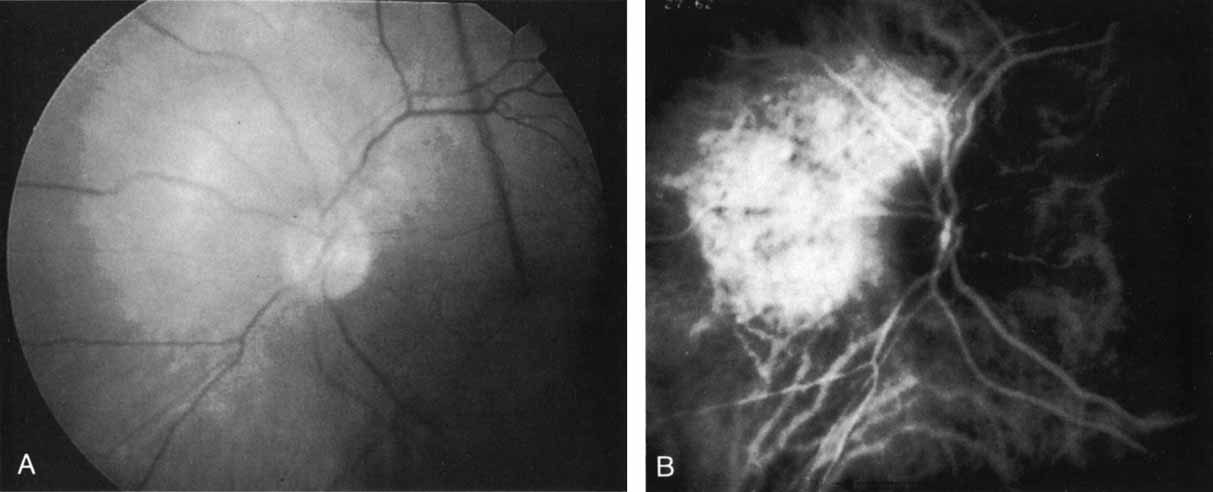

In a landmark article, Yannuzzi and associates18 demonstrated that ICG videoangiography was extremely useful in identifying well-demarcated localized areas of neovascularization in what had been classified as occult CNV by standard fluorescein angiography.19–24 In this study, 39% of 129 patients with “occult CNV” originally diagnosed as determined by fluorescein angiography were given a revised diagnosis of “well-defined neovascular lesions” based on the information obtained from the ICG study (Fig. 1). One study revealed that approximately 40% of patients with occult CNV diagnosed actually presented with early, well-defined focal areas of fluorescence on ICG videoangiography.25 They further defined two potential subgroups of occult CNV: those with and those without serous pigment epithelial detachments (PEDs) accompanying the occult neovascular process. They also pointed out that ICG angiography offered a potential advantage in identifying neovascular lesions when there was clinical evidence of recurrent CNV after previous laser photocoagulation treatment.

Subsequently, Yannuzzi and colleagues25 and Guyer and associates26 evaluated the usefulness of ICG angiography in identifying localized areas of CNV in patients with occult CNV with or without a serous PED. In a careful evaluation of more than 680 patients, they identified 22% of patients with localized lesions that might be amenable to laser therapy—lesions that would otherwise be classified as untreatable based on guidelines for laser photocoagulation (Figs. 2 and 3). As a result of this improved imaging technique, as many as two to three times the number of patients would have been potentially eligible for laser treatment than would have been treatable based on fluorescein angiography alone.